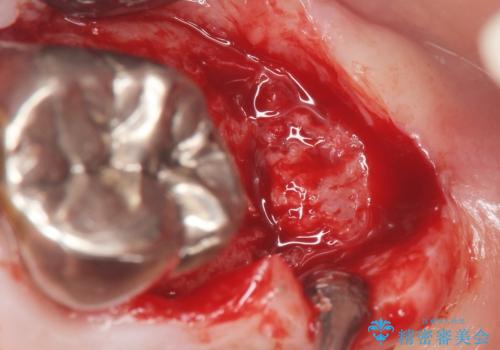

患者様のご希望により抜歯してインプラントによる治療を行いました。

上顎洞が近接しており上顎骨の厚みが薄いことから、ソケットリフト(上顎洞底挙上術)をインプラント埋入と同時に行いました。

ソケットリフトにより上顎洞底を挙上し骨造成することにより、骨の厚みが薄い部分でもインプラントが可能になります。